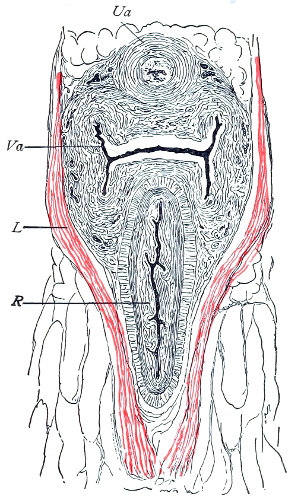

The vagina extends, as a transverse slit in the pelvic floor, upward and backward, approximately in the direction 60 of a line drawn from the ostium vaginæ to the fifth sacral vertebra. It is approximately parallel with the conjugate of the brim, so that when the woman is erect the long axis of the vagina is inclined at an angle of 60° to the horizon. The vagina is not a vertical open tube: it is a slit in the pelvic floor, in health always closed by the accurate apposition of the anterior and posterior walls (Fig. 21). The anterior vaginal wall is about 2½ inches long in a vertical mesial line. The posterior vaginal wall is about 3½ inches long. The vaginal walls are triangular in shape, being broader above than below. The shape of the normal vagina at the pelvic outlet is shown by Fig. 23. The section here shows the vaginal 61 slit of the shape of the letter H. The portions of the slit extending backward and somewhat outward are called the vaginal sulci or furrows. They are directions of diminished resistance in which tears are liable to occur.

Fig. 23.—Section illustrating the characteristic form of the vaginal cleft (Henle): Ua, urethra; Va, vagina; L, levator ani; R, rectum.] 62